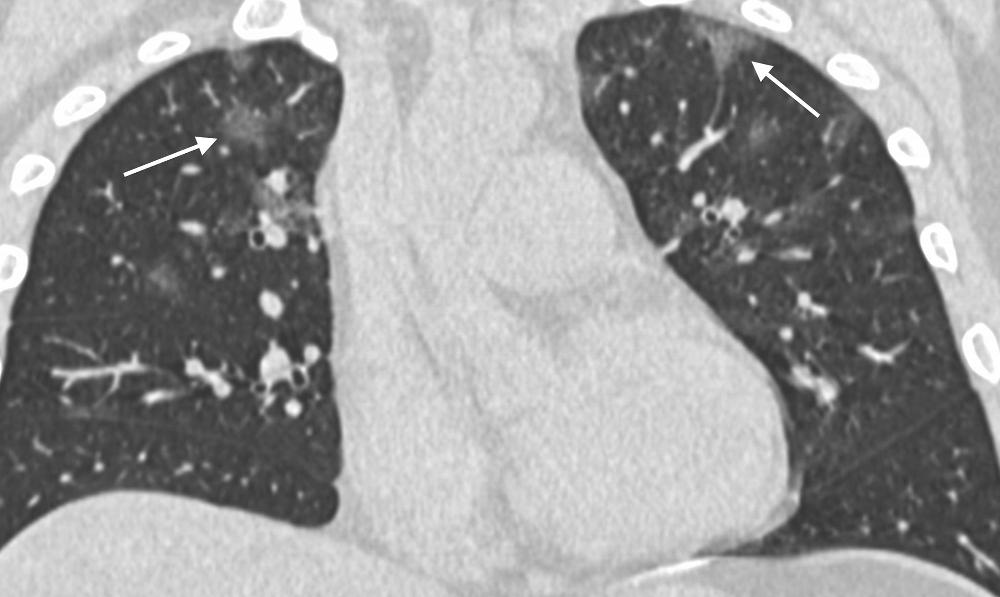

Figure 2. 36-year old male with history of recent travel to Wuhan, presenting with fever, fatigue and myalgias. Coronal thin-section non-contrast CT image shows ground-glass opacities with a rounded morphology in both upper lobes (arrows).